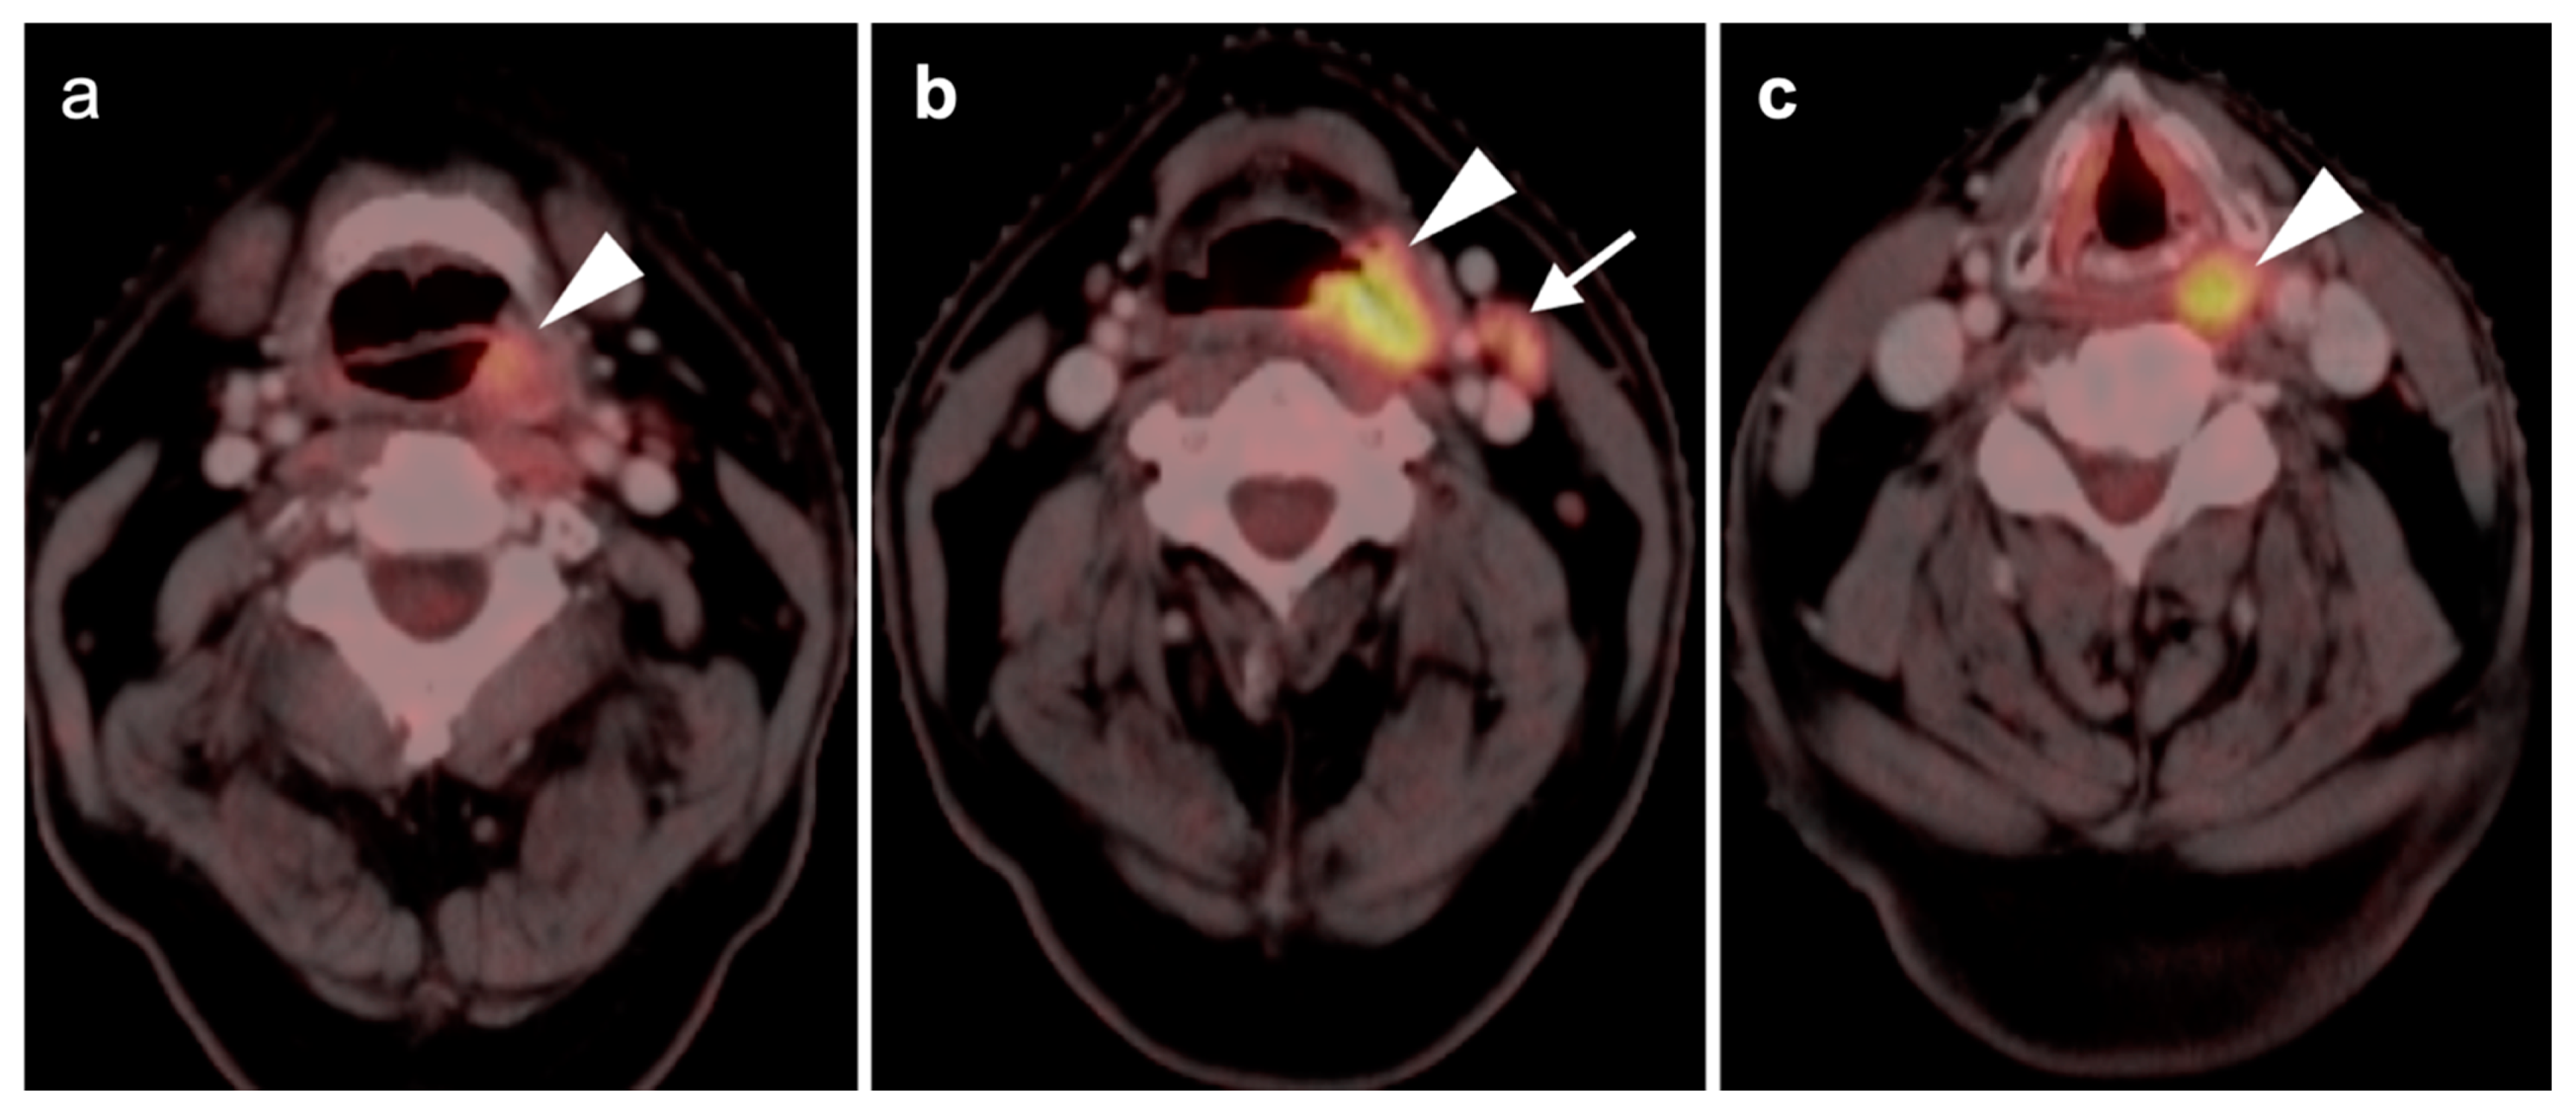

2.6. Thyroid Cancer

- Differentiated thyroid cancer

- Medullary thyroid cancer